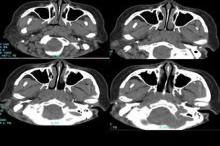

上颌窦CT解剖示意图

上颌窦是上颌骨体内一个锥形空腔,窦壁由骨质构成,多数是薄薄的密质骨板而内部略呈松质骨状。